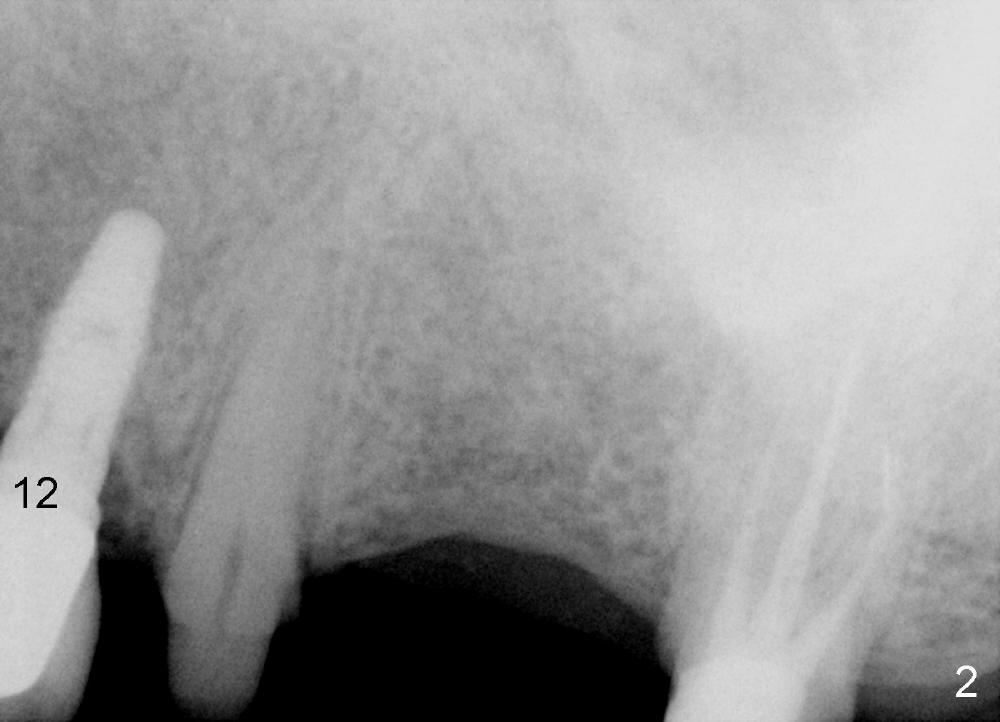

A 71-year-old male is a bruxer. His upper left fixed partial denture was lost 4 years ago (Fig.2). It is replaced by an implant (Fig.3: #14) and two single unit crowns (#13,15). One year later, the tooth #5 is replaced by an immediate implant due to crown fracture (Fig.1,4). Six months after the cementation of #5 implant crown, the tooth #15 is restored by an immediate implant due to root fracture (Fig.6). Recently, porcelain chips off the PFM crown of #13. The patient finally agrees to have another implant (Fig.1: #2) to make his dentition complete and distribute masticatory force more evenly.

The advantage to place implants for a bruxer is that there is sufficient bone height (Fig.2-4). The bone density also appears to be high; there is a thick cortical bone in the edentulous ridge of #2 (Fig.4 arrowheads). Incision will be made; suture may be required for flap fixation. Osteotomy is initiated by 2 mm pilot drill 4 mm from the neighboring tooth (Fig.5); the depth is 8 mm. The depth of the osteotomy is adjusted according to X-ray taken with a parallel pin. Sinus lift may be needed (Fig.5 dashed line: sinus floor). The density of the cancellous bone will be felt and determined while using the 2 mm pilot drill for initial osteotomy. If the density is high, Bicon reamers will be used for further osteotomy and bone saving. Otherwise, osteotomy will be finished mainly with Bone Expander Kit or osteotomes. Bone-level implant is used, followed by a healing abutment. Decortication will be done with a surgical handpiece with a fissure or round bur. If no suture is used for flap fixation, perio glue will be used to close the incision without perio dressing. If the wound is not approximated each other well with sutures, perio glue can be used for complete seal.